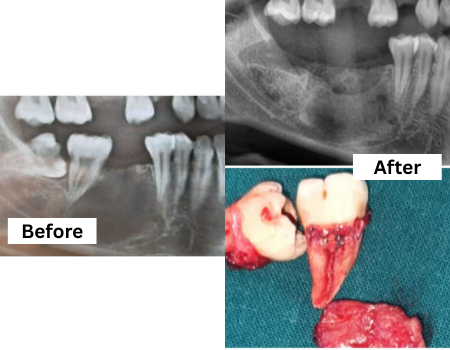

Wisdom Tooth Surgery

Safe, precise removal of impacted or problematic wisdom teeth to prevent pain, infection, and misalignment of surrounding teeth.